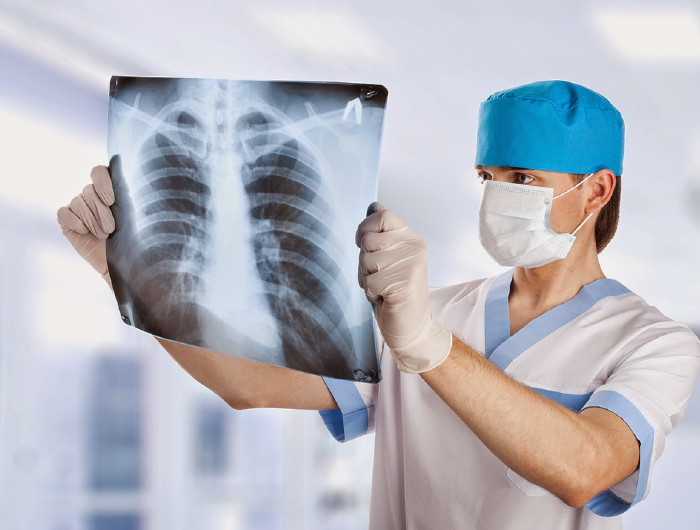

La radiología es una rama de la medicina que utiliza la tecnología imagenológica para diagnosticar y tratar una enfermedad. Se puede dividir en dos áreas diferentes: radiología diagnóstica y radiología intervencionista. Los médicos que se especializan en radiología se denominan radiólogos.

Estudios que realizamos

Se realizan, entre otros, los siguientes estudios radiológicos no contrastados (de frente/perfil/oblicuo/parado o acostado):